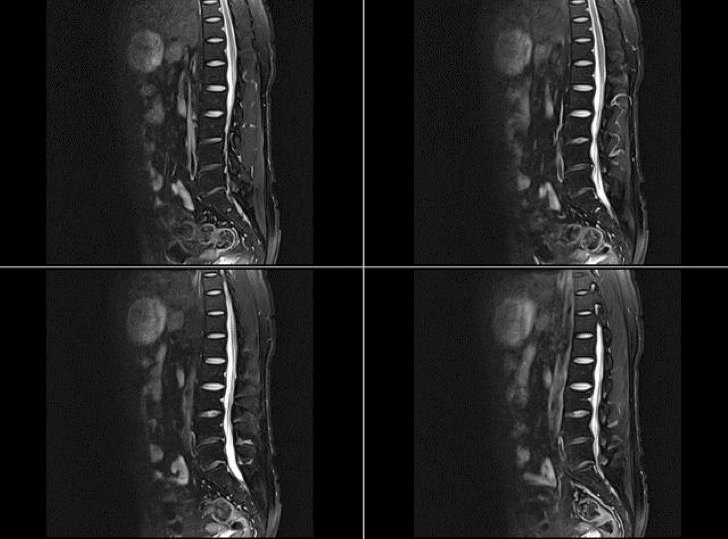

Lumbar Region Fat suppression Images